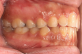

Dentición mutilada

La falta de soporte posterior y de unidades de anclaje apropiadas, la pérdida de dimensión vertical, la presencia de prótesis fijas o removibles, la intervención endodóntica y la condición periodontal comprometida, todo ello contribuye a la complejidad. Para mover los dientes anteriores debe existir dentición posterior estable que pueda usarse como anclaje. Puentes múltiples, restauraciones o dientes ausentes contribuyen a una reducción del anclaje y, por tanto, a un resultado menos predecible.